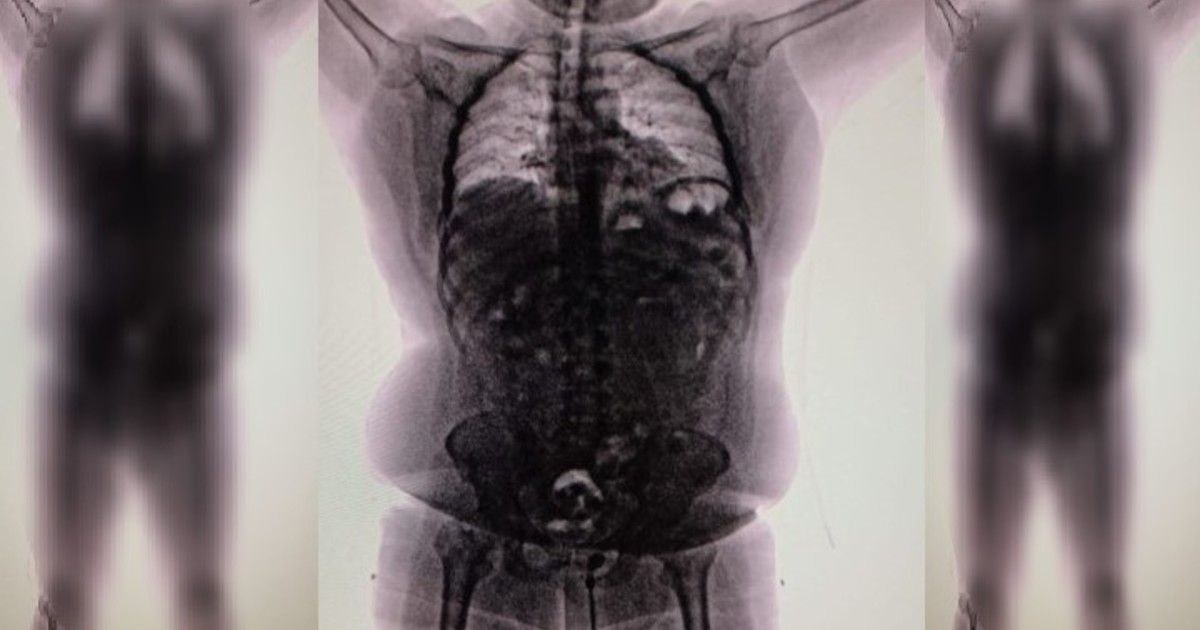

• El hombre, de 30 años, se ingestó en Perú, viajó a Buenos Aires, cambió de aeropuerto y en Ezeiza trató de embarcar rumbo a Milán con escala en Frankfurt.

• La “mula” fue descubierta y estuvo internada cuatro días. Expulsó 90 cápsulas que contenían 698 gramos de cocaína.